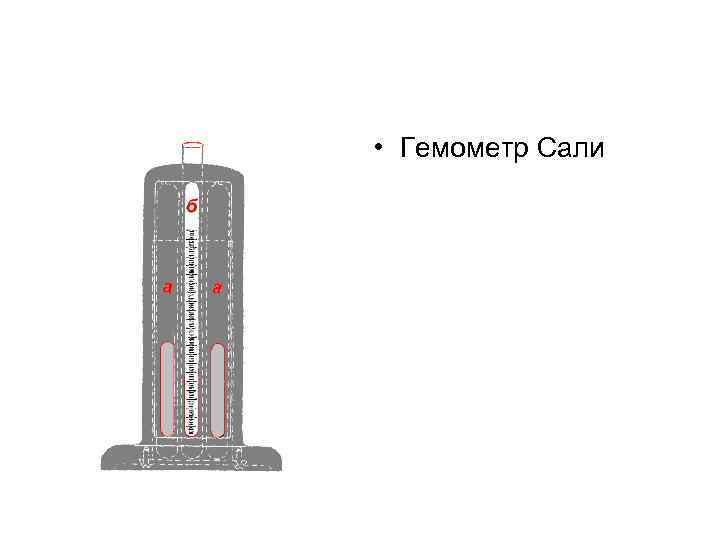

• Гемометр Сали

• Гемометр Сали